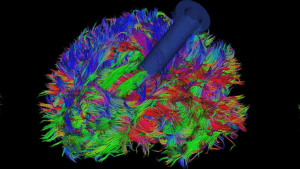

Robert Louis, MD is one of the few brain surgeons in Orange County to use NICO BrainPath™, a revolutionary technology that provides access and visualization of tumors, cysts, lesions, or blood clots in the subcortical region of the brain. This innovative tool places a tube that safely creates a path to the surgical area, allowing your brain surgeon to move through the natural and delicate folds, tissues, and fibers of the brain to access and remove tumors, lesions, or blood clots and resection of soft tissues, giving patients better chance at survival.

Robert Louis, MD is one of the few brain surgeons in Orange County to use NICO BrainPath™, a revolutionary technology that provides access and visualization of tumors, cysts, lesions, or blood clots in the subcortical region of the brain. This innovative tool places a tube that safely creates a path to the surgical area, allowing your brain surgeon to move through the natural and delicate folds, tissues, and fibers of the brain to access and remove tumors, lesions, or blood clots and resection of soft tissues, giving patients better chance at survival.

NICO BrainPath™ is uniquely designed with an atraumatic tip that minimizes tissue damage by displacing tissues of the brain during advancement to the targeted location in the brain. The sheath remains in the brain after the obturator is removed to serve as a protective portal for surgeons to easily maintain access to the surgical site. Once in place, it creates a passageway for Dr. Louis to access the surgical site and then use a resection tool to remove the tumor, lesion, or blood clot. This new treatment integrates other technologies such as brain imaging, neuro-navigation, and optics

Innovative technology that provides Dr. Louis safe access to the subcortical region of the brain through a smaller opening. The clear sheath remains in the brain during the entire procedure to serve as a protective portal for your brain surgeon to easily maintain access to the surgical site.